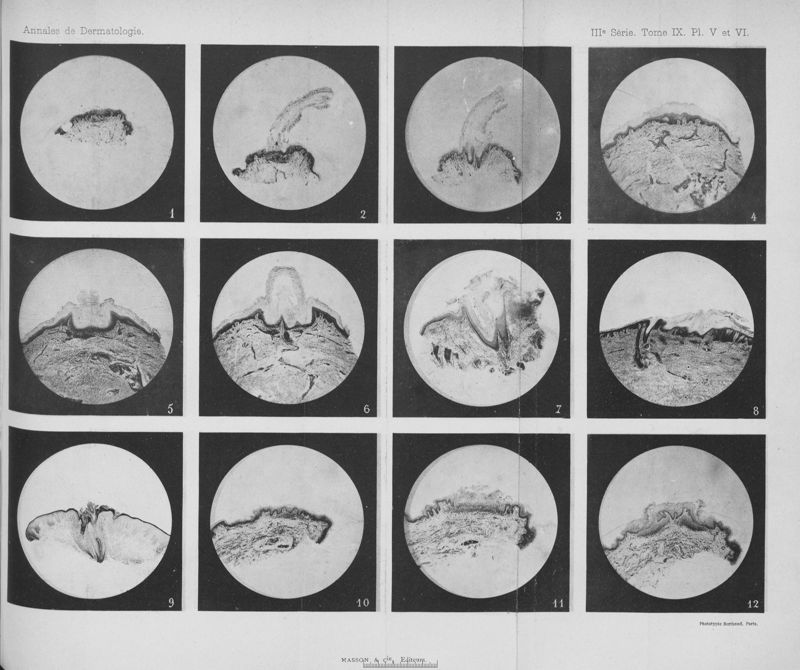

Annales de dermatologie et de syphiligraphie

3ème série, tome IX. - Paris : Masson, 1898.